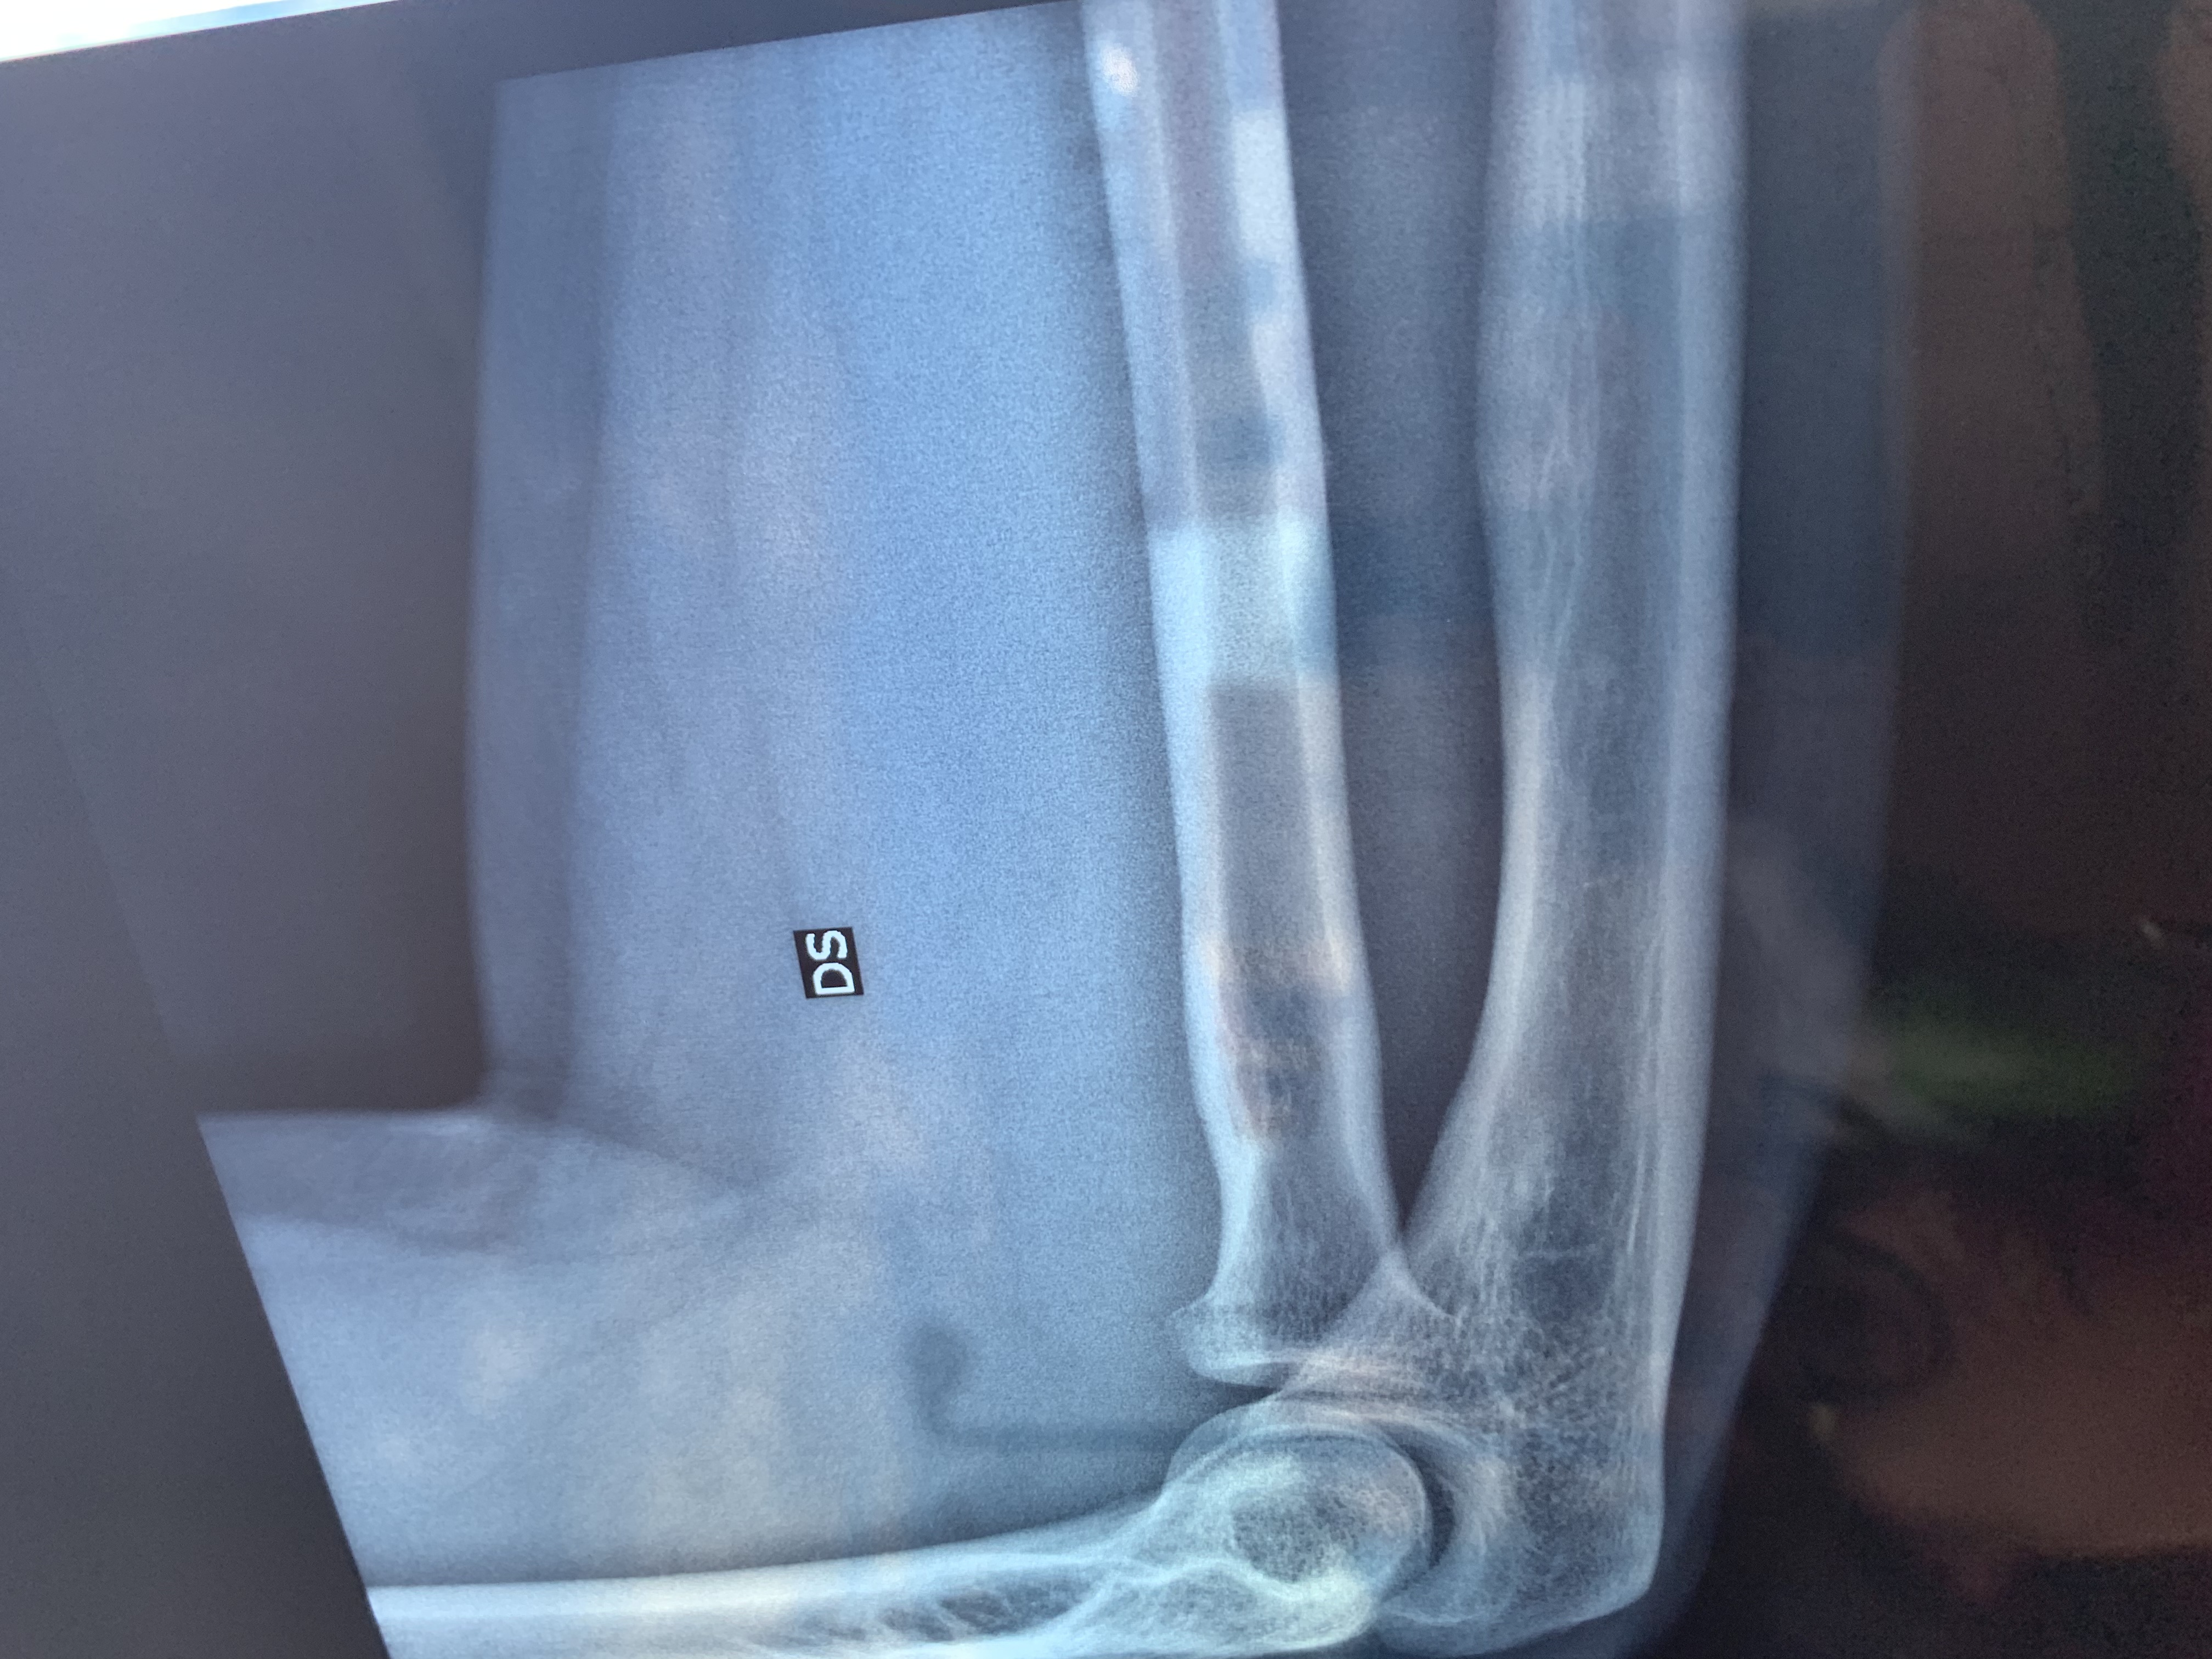

Commento file: Seconda lastra

Buonasera, ieri in data 21 maggio mentre giocavo a calcetto tra amici, purtroppo durante un contrasto sono caduto.. il peso del corpo è caduto tutto sul mio braccio destro, ho sentito in un primo impatto un dolore lancinante, però subito dopo ho continuato a giocare a mia insaputa della gravità del problema, ho continuato a giocare per circa 1 ora, senza alcun evidente problema. Tornato a casa applico una pomata antinfiammatoria e una fascia che immobilizza non totalmente il gomito. In mattina mi reco in pronto soccorso,dagli esami rx viene rilevata una frattura composta del capitello radiale dx con componente intra-articolare con seguente visita ortopedica con immediata doccia gessata per 25 giorni . L

Commento file: Prima lastra